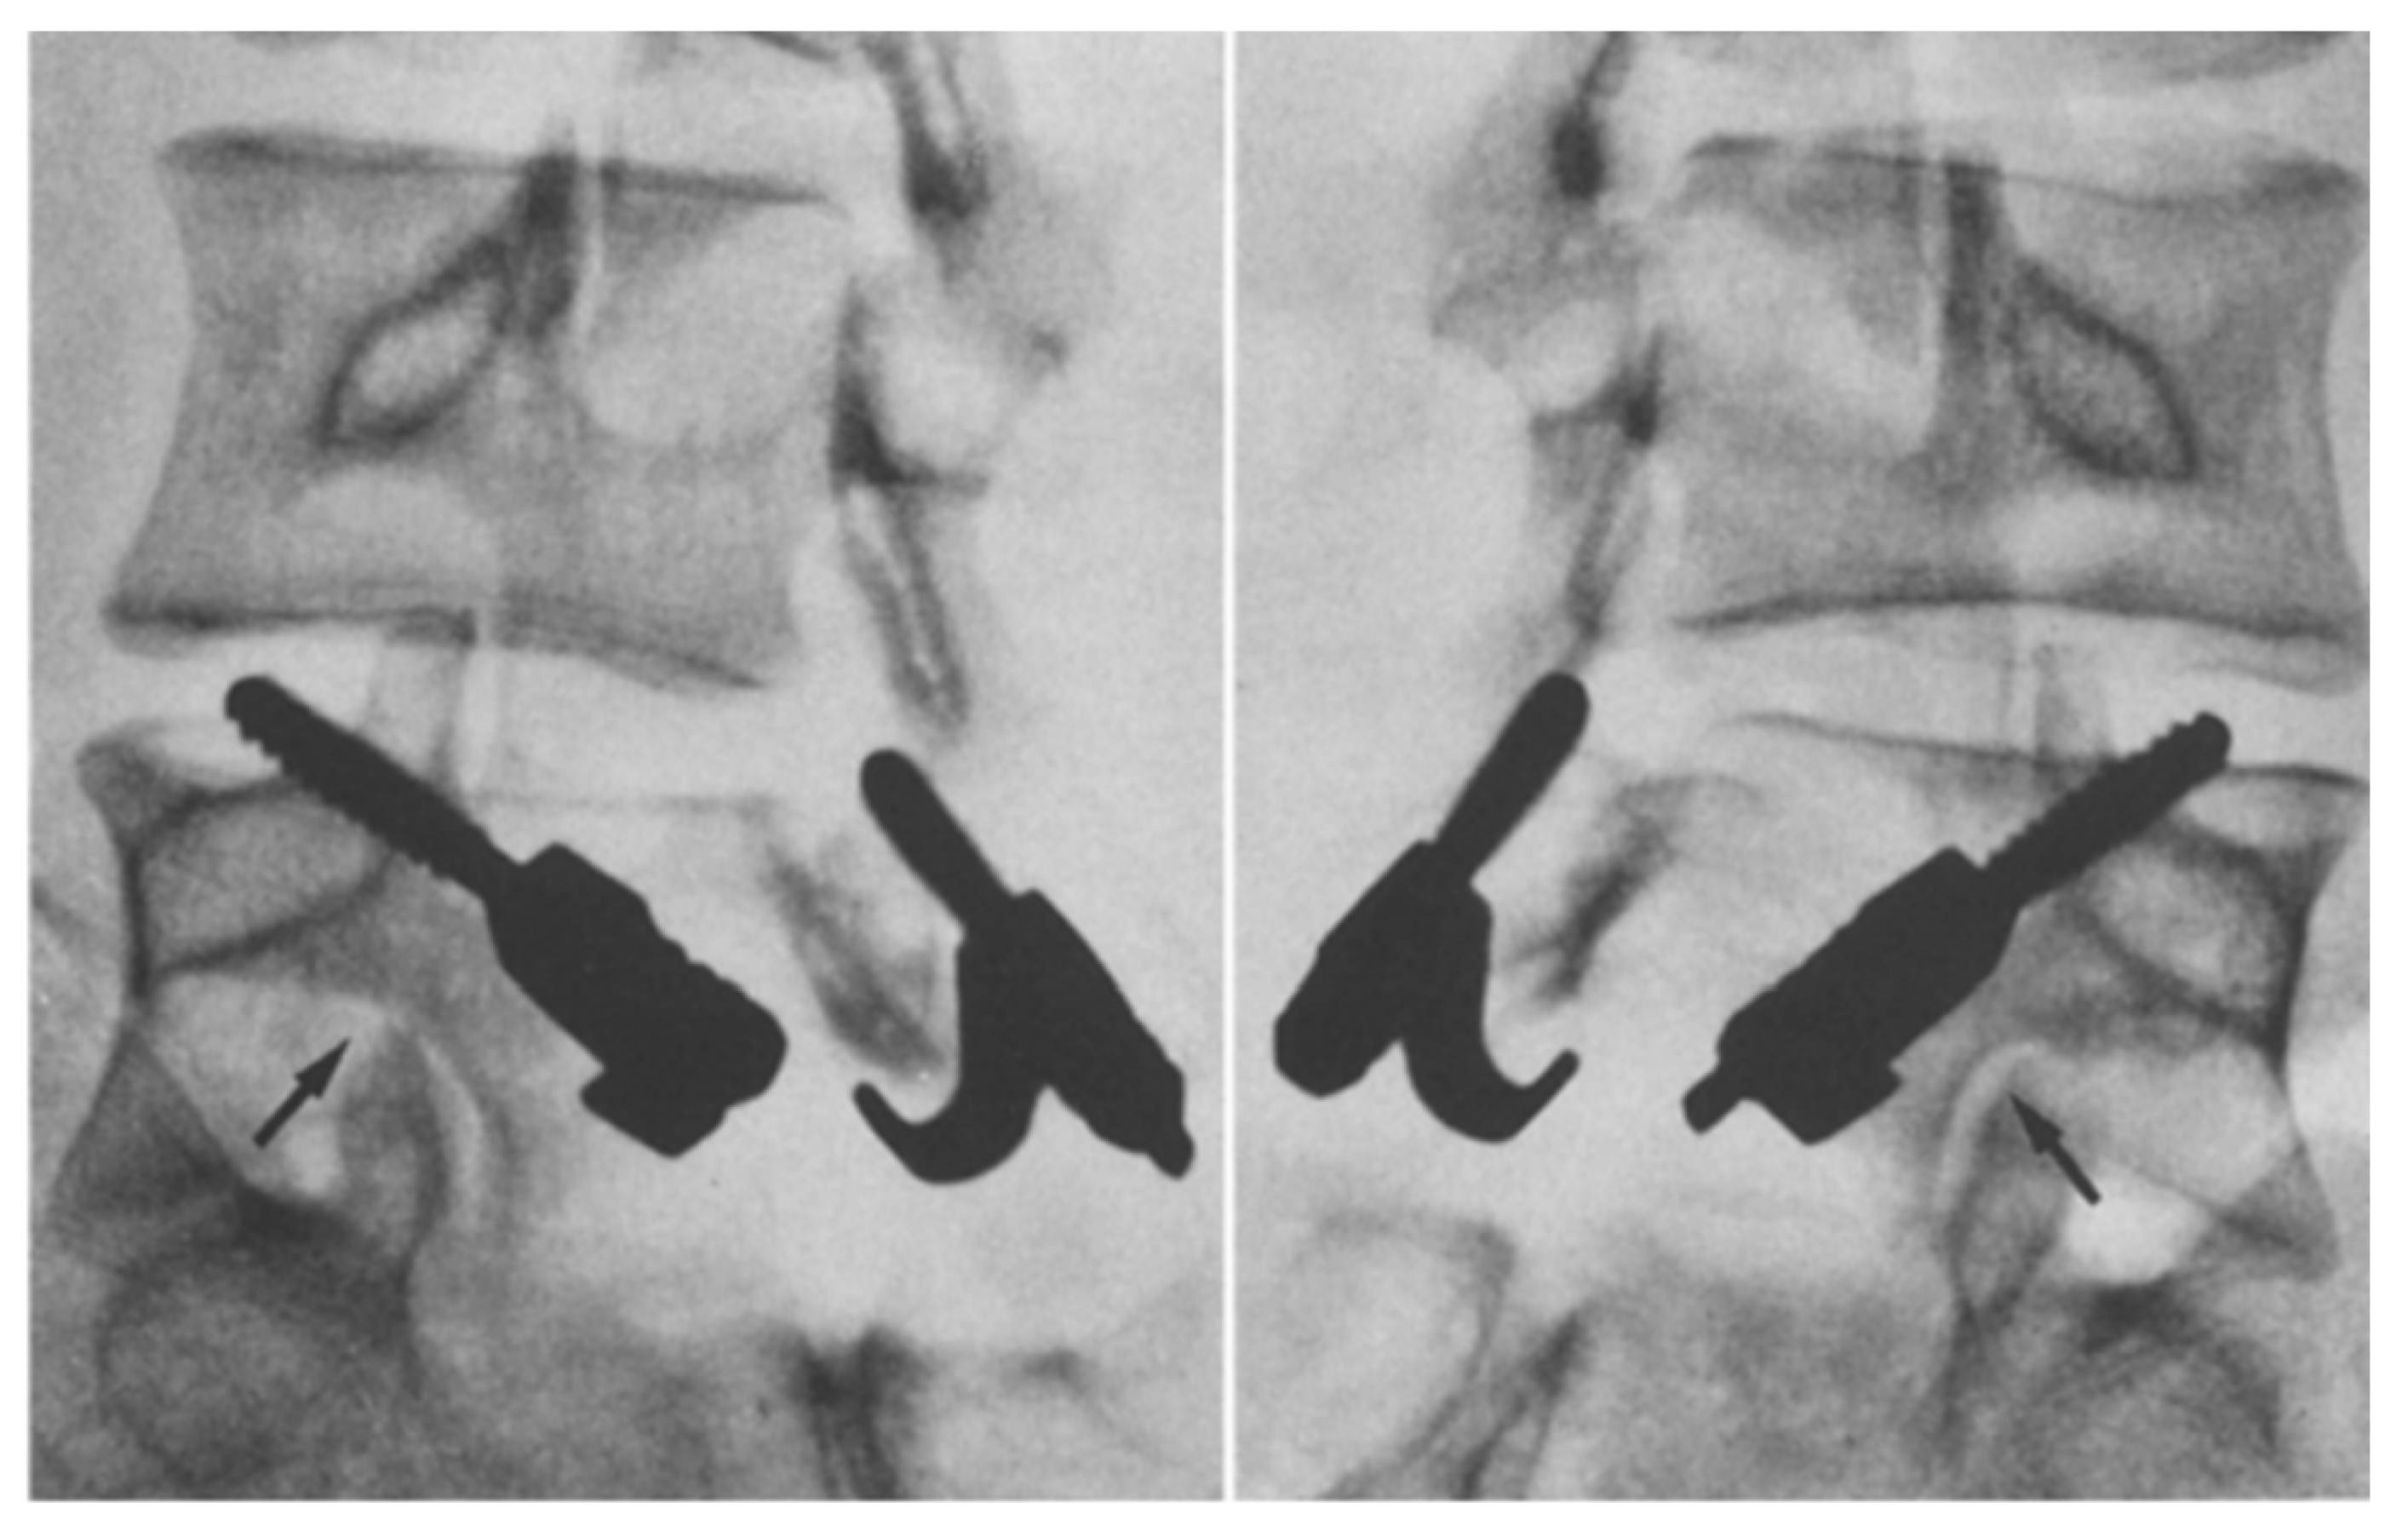

1.9.3. Scott’s Wiring Technique

- Nicol, R.O.; Scott, J.H. Lytic spondylolysis. Repair by wiring. Spine 1986, 11, 1027–1030. [Google Scholar] [CrossRef]

- Johnson, G.V.; Thompson, A.G. The Scott wiring technique for direct repair of lumbar spondylolysis. J. Bone Jt. Surg. Br. Vol. 1992, 74, 426–430. [Google Scholar] [CrossRef]

- Hioki, A.; Miyamoto, K.; Sadamasu, A.; Nozawa, S.; Ogawa, H.; Fushimi, K.; Hosoe, H.; Shimizu, K. Repair of pars defects by segmental transverse wiring for athletes with symptomatic spondylolysis: Relationship between bony union and postoperative symptoms. Spine 2012, 37, 802–807. [Google Scholar] [CrossRef] [PubMed]